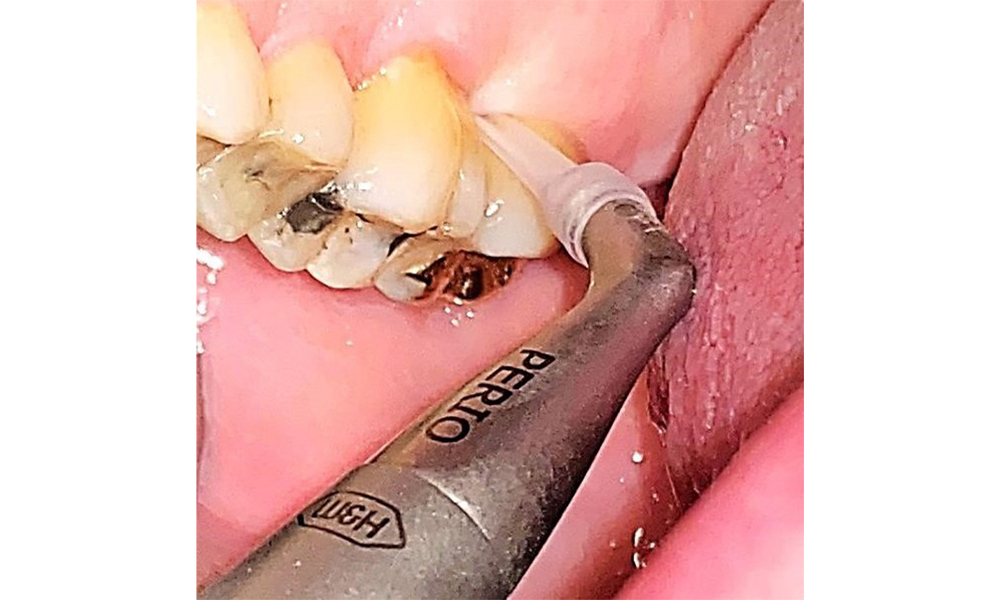

There are no limitations regarding the choice of instrumentation methods. Regular supragingival and subgingival instrumentation is essential to prevent disease progression due to the pre-existing periodontitis and high risk of recurrence. There are no limitations placed on the selection of instruments for mechanical biofilm removal from a general medical perspective, and removal should be performed as needed. Hard and mineralized plaque, such as calculus and concretions, should be removed using manual instruments or sonic/ultrasonic scalers (Fig. 9) (8, 9).

Supragingival and subgingival biofilm removal is indispensable for maintaining the stability of the periodontal condition. Air polishing using low-abrasive powder is suitable for this purpose. Periodontal pockets and exposed root surfaces must be cleaned with low-abrasion powders. The use of a flexible parotip is recommended for patients with increased probing depths (deeper than 5 mm) (Fig. 10). (9)